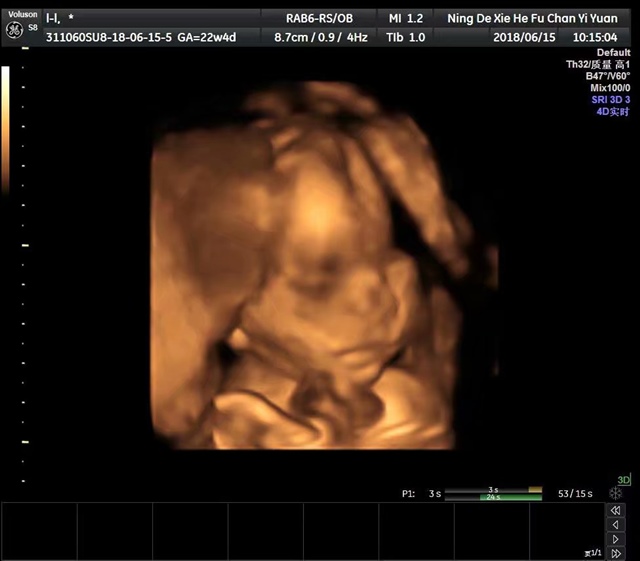

孕22周+3天

女宝么